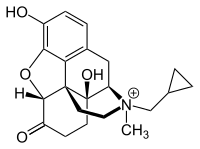

The pharmacodynamic response to an opioid depends upon the receptor to which it binds, its affinity for that receptor, and whether the opioid is an agonist or an antagonist. For example, the supraspinal analgesic properties of the opioid agonist morphine are mediated by activation of the μ1 receptor; respiratory depression and physical dependence by the μ2 receptor; and sedation and spinal analgesia by the κ receptor. Each group of opioid receptors elicits a distinct set of neurological responses, with the receptor subtypes (such as μ1 and μ2 for example) providing even more [measurably] specific responses. Unique to each opioid is its distinct binding affinity to the various classes of opioid receptors (e.g. the μ, κ, and δ opioid receptors are activated at different magnitudes according to the specific receptor binding affinities of the opioid). For example, the opiate alkaloid morphine exhibits high-affinity binding to the μ-opioid receptor, while ketazocine exhibits high affinity to ĸ receptors. It is this combinatorial mechanism that allows for such a wide class of opioids and molecular designs to exist, each with its own unique effect profile. Their individual molecular structure is also responsible for their different duration of action, whereby metabolic breakdown (such as N-dealkylation) is responsible for opioid metabolism.

Several semi-synthetic opioids were developed in Germany in the 1910s. The first, oxymorphone, was synthesized from thebaine, an opioid alkaloid in opium poppies, in 1914.[228] Next, Martin Freund and Edmund Speyer developed oxycodone, also from thebaine, at the University of Frankfurt in 1916.[229] In 1920, hydrocodone was prepared by Carl Mannich and Helene Löwenheim, deriving it from codeine. In 1924, hydromorphone was synthesized by adding hydrogen to morphine. Etorphine was synthesized in 1960, from the oripavine in opium poppy straw. Buprenorphine was discovered in 1972.[228]